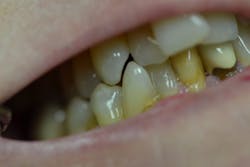

Figure 2: Mandibular arch

Her periodontal probing depths ranged from 2 mm to 6 mm, with as much as 4 mm of recession noted in some areas. Tooth No. 19 had a fractured off DL cusp to the gumline with decay close to the nerve; No. 29 had deep DO decay that would require endodontic treatment, buildup, and a crown to repair or possibly extraction; and No. 31 was unrestorable with buccal decay to the nerve, through the furcation, and at the bone level (figures 1–6). Faced with that treatment plan, she would also need four quads of scaling and root planing with anesthetic. We were able to coordinate the schedule to extract No. 31 directly after her periodontal treatment while she was still anesthetized.